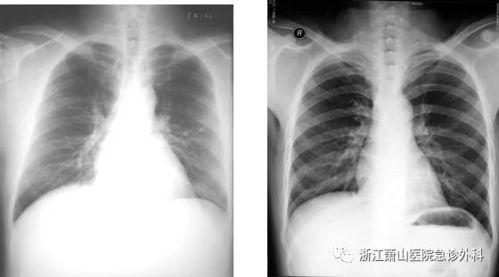

CT扫描具有卓越的密度分辨率,能够区分不同组织之间的密度差异。这对于诊断骨骼、软组织、血管等部位的病变具有重要意义。在X光检查中,由于密度分辨率较低,一些细微的病变可能无法被发现。

CT扫描适用于各种疾病的诊断,如神经系统、心血管系统、呼吸系统、消化系统、泌尿系统等。在X光检查中,由于图像质量有限,一些疾病的诊断可能存在困难。而CT扫描可以提供更全面、准确的诊断信息。